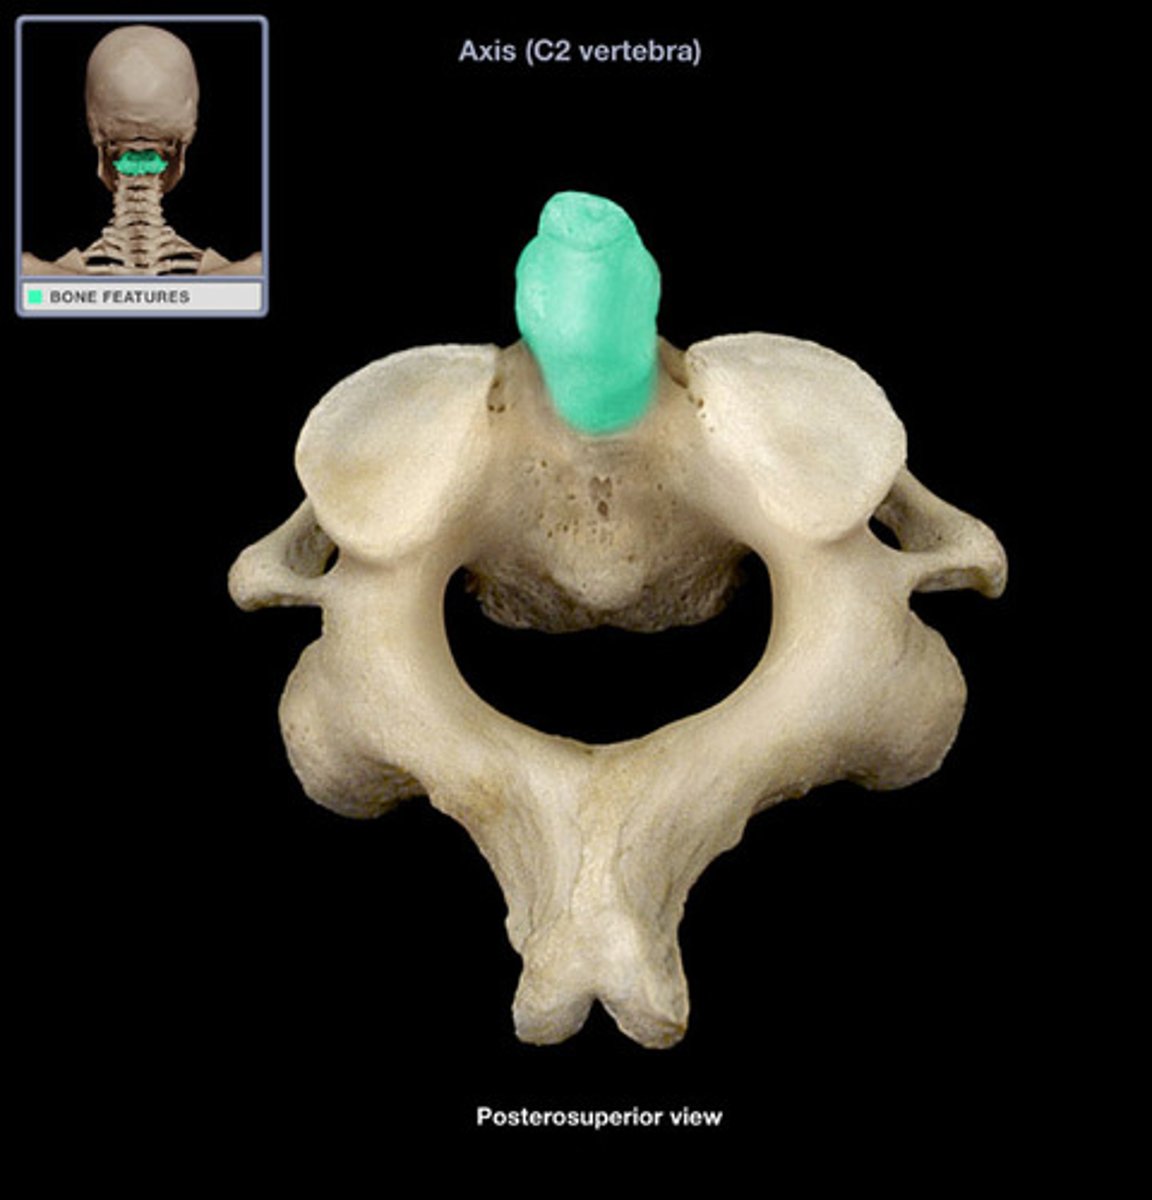

axis C2

C2

what vertebra is considered the axis

allows u to turn head

what is purpose of c2

adontoid process (dens)

what structure allows for head rotation in C2

adontoid process (dens)